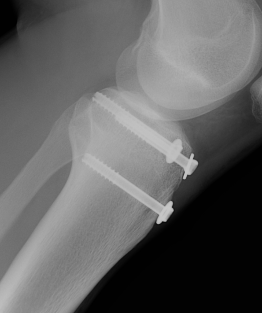

Type I /Type II

Technique

Screw +/- anchor fixation +/- tension band fixation of tibial tubercle and patella tendon

- screw +/- washer in fragment if large

- can supplement with Krackow sutures in patella tendon and fixed distally with suture anchors

Fixation

Arkader et al J Pediatr Orthop 2019

- 90 fractures treated with screw fixation

- 100% union

- no difference in unicortical versus bicortical fixation